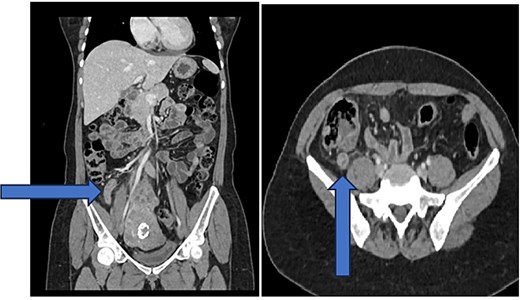

On examination, she was afebrile and stable, with localized right iliac fossa tenderness, rebound tenderness, mild epigastric tenderness, and a positive Rovsing’s sign. Labs showed a white blood cell count of 10.4 × 109/L and C-reactive protein of 45 mg/L. Contrast-enhanced computed tomography (CT) revealed an 11 mm dilated appendix with mural enhancement, minimal fat stranding, slight free fluid, and small mesenteric lymph nodes, consistent with uncomplicated acute appendicitis (Fig 1).